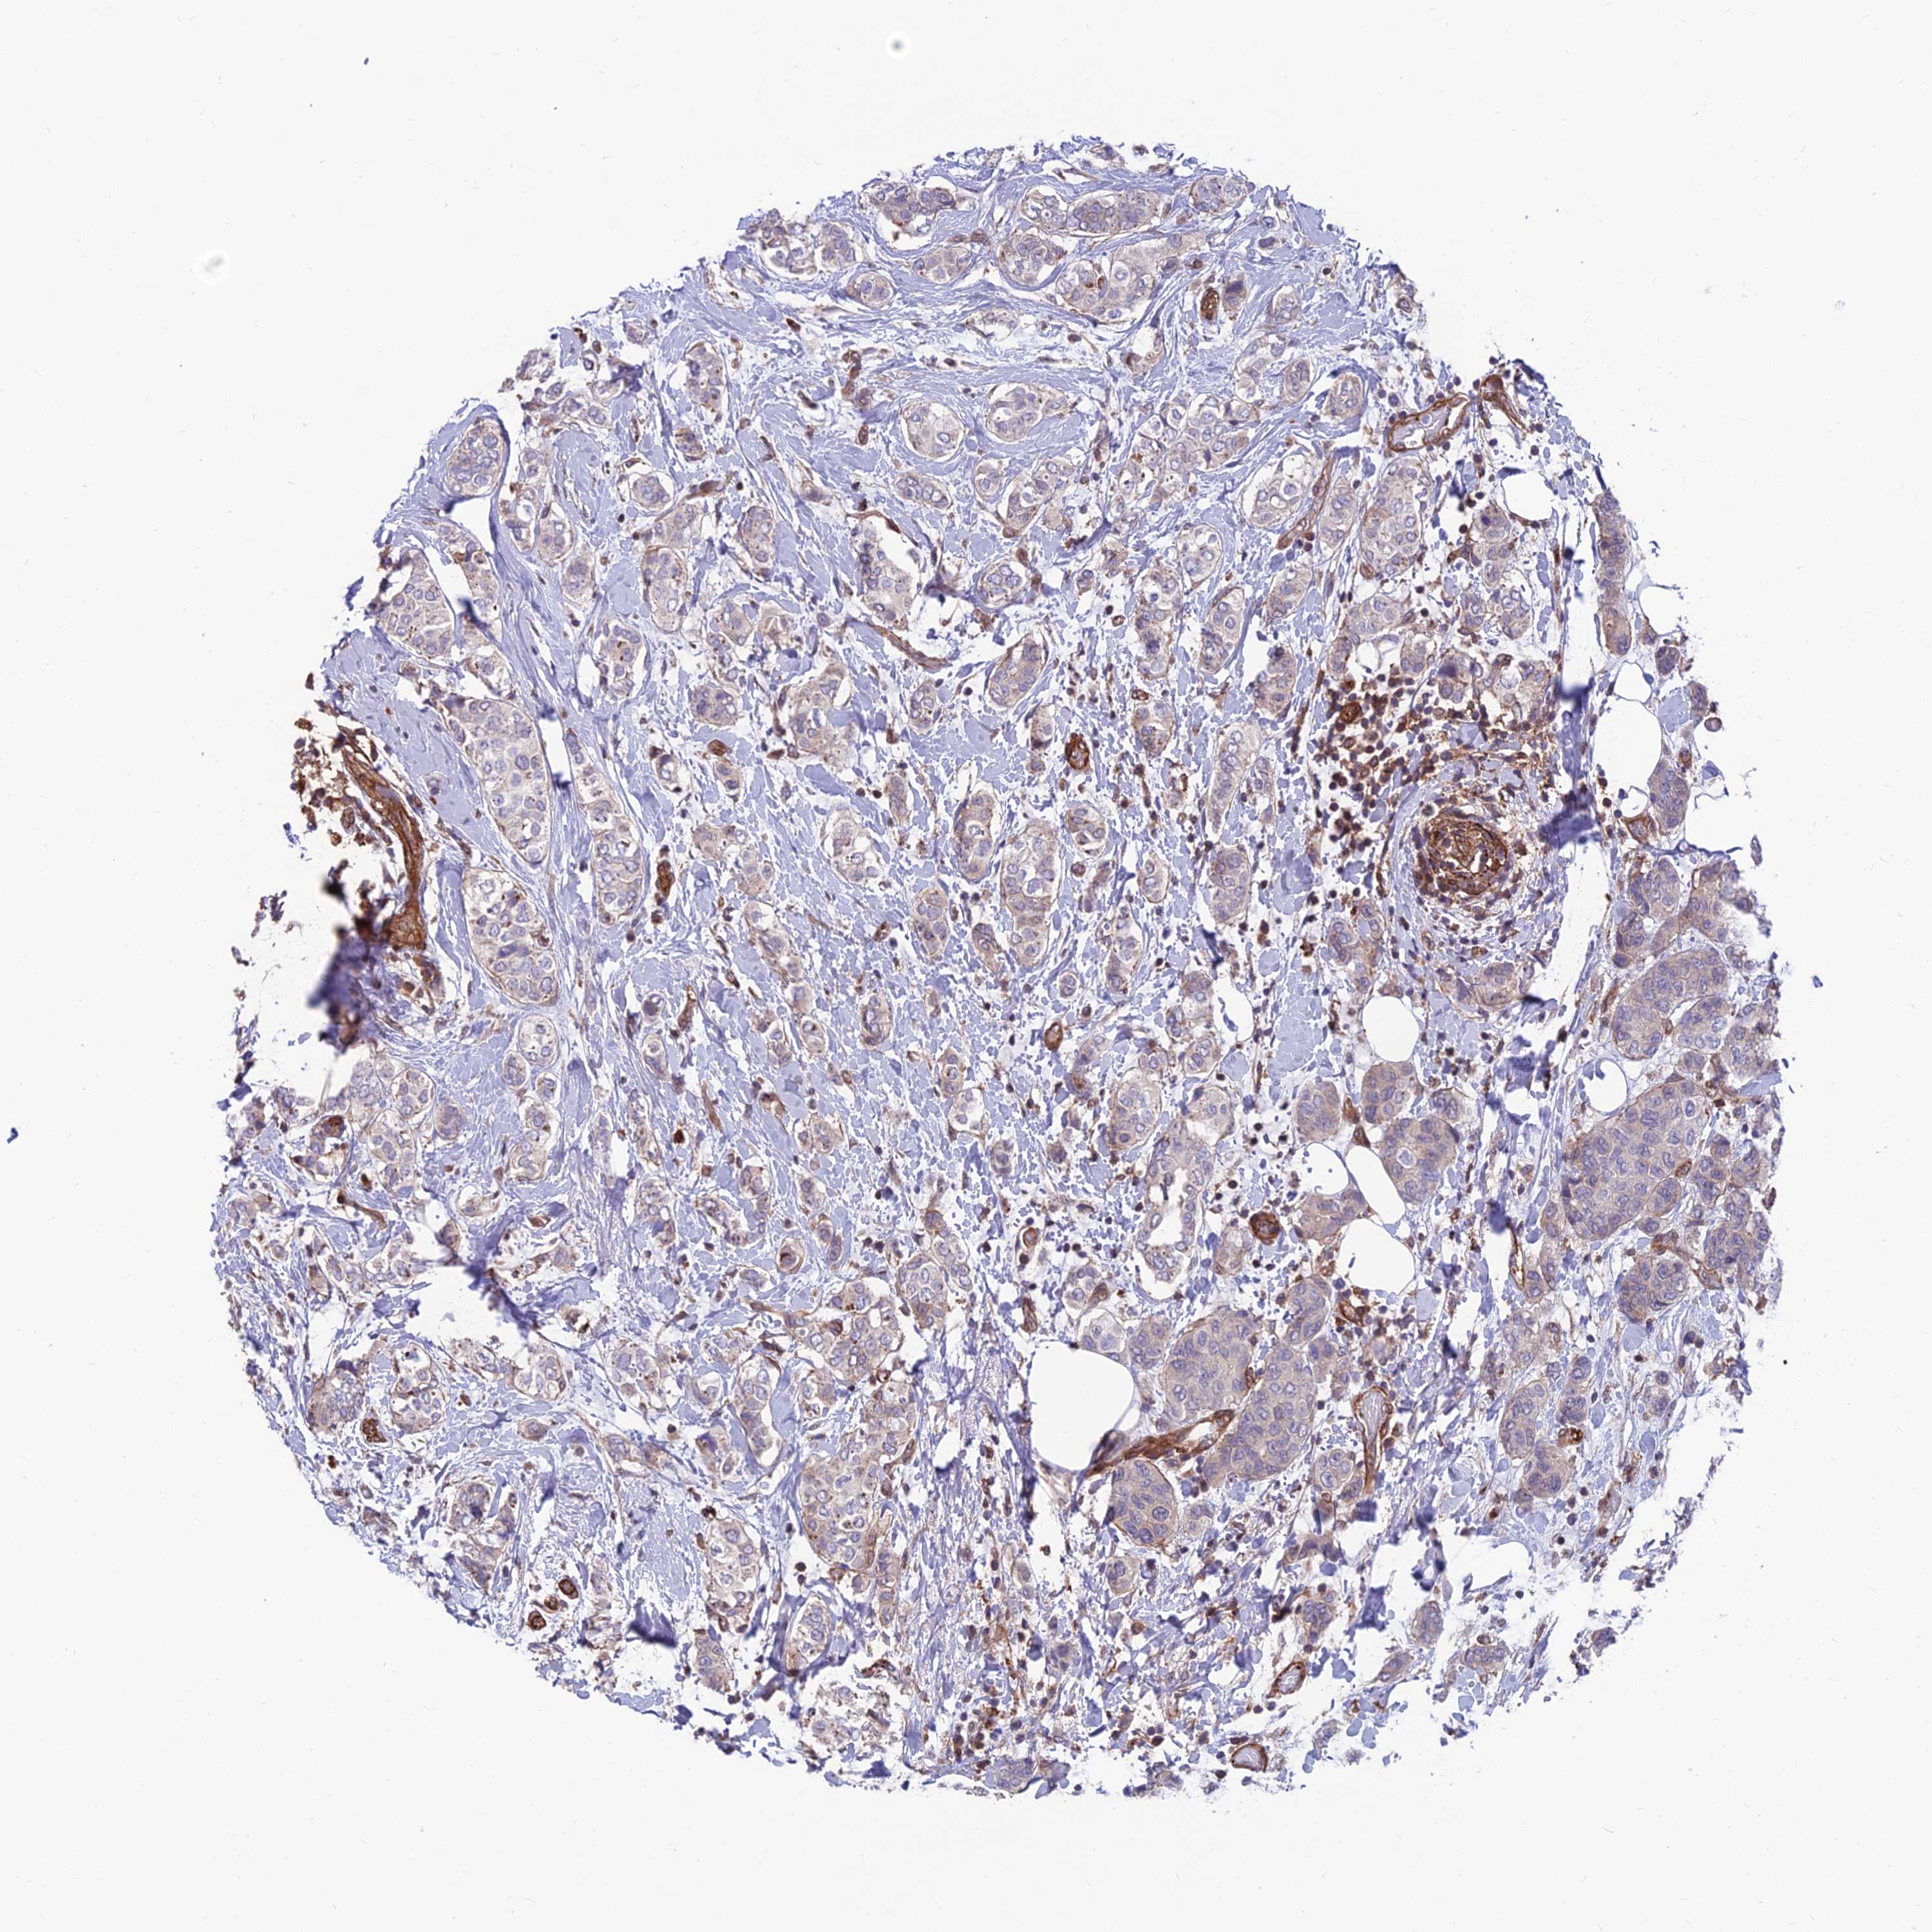

CANCER BREAST CANCER Show tissue menu

BRCA TCGA BRCA VALIDATION PROTEIN EXPRESSION